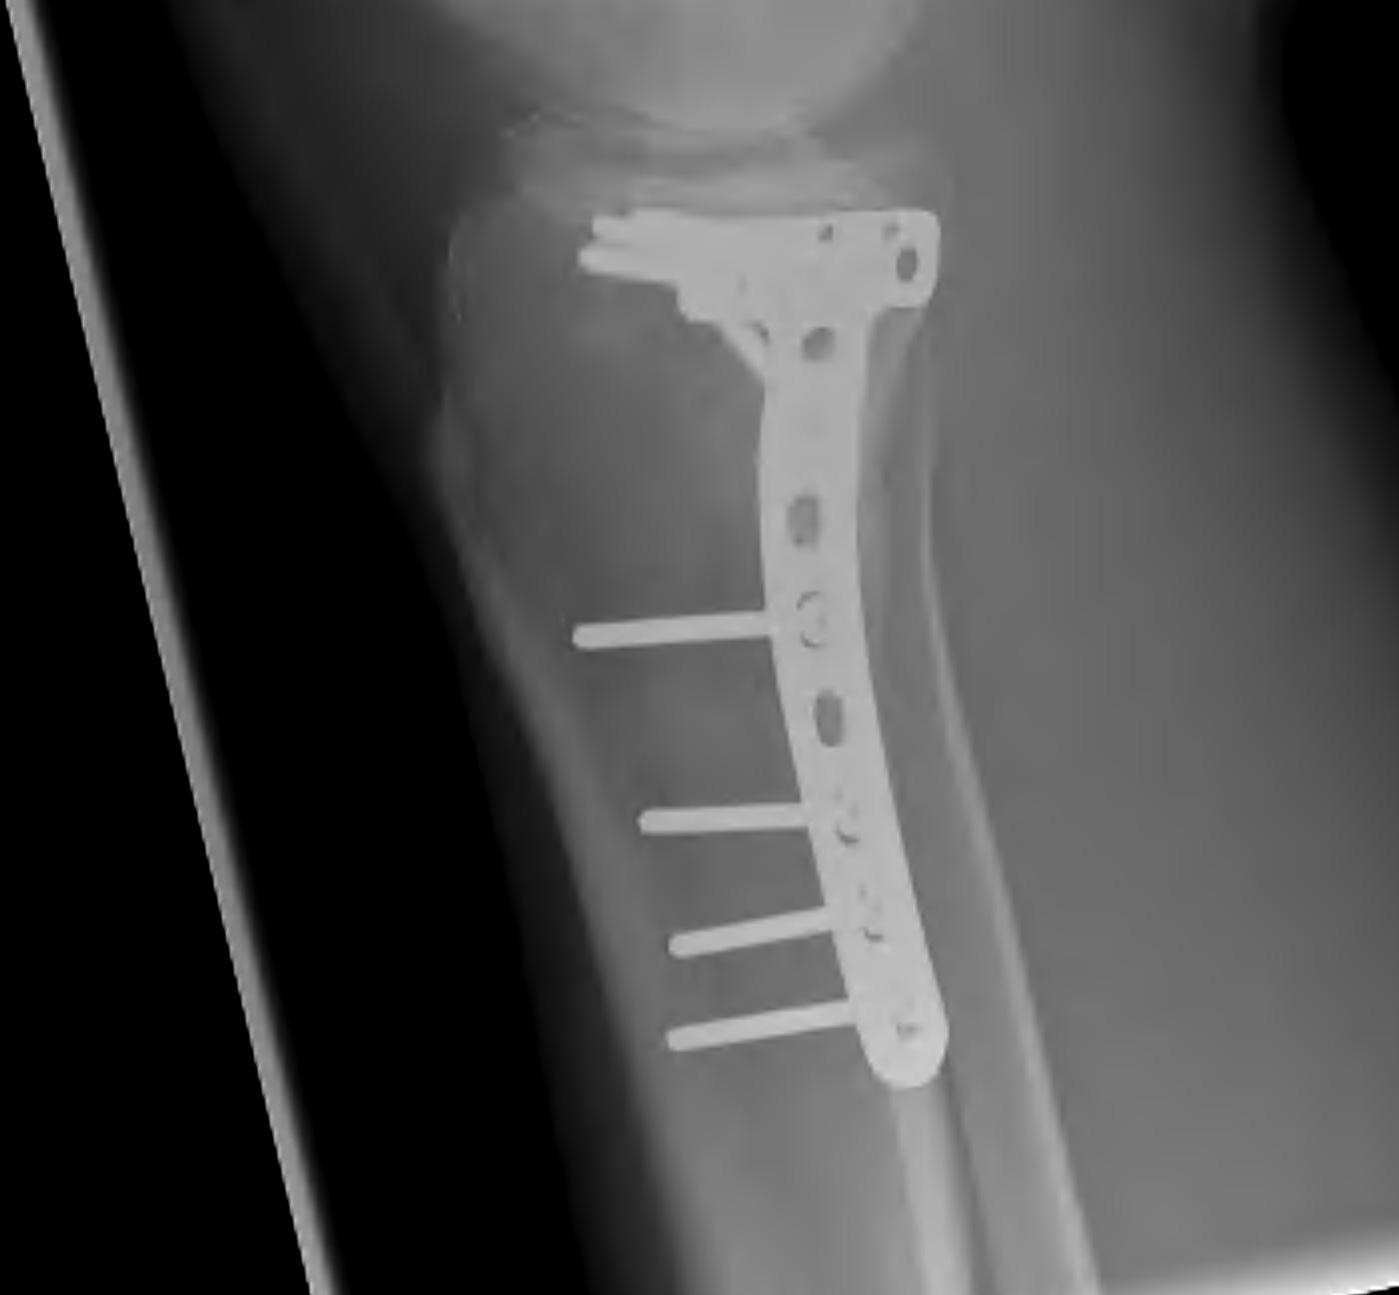

Type IV Medial Condyle

Technique

Medial approach

- make incision 1 cm from posterior edge of tibia

- release and reflect MCL posteriorly

- partially release pes anserinus / reflect inferiorly

- T plate

- can slide under the pes